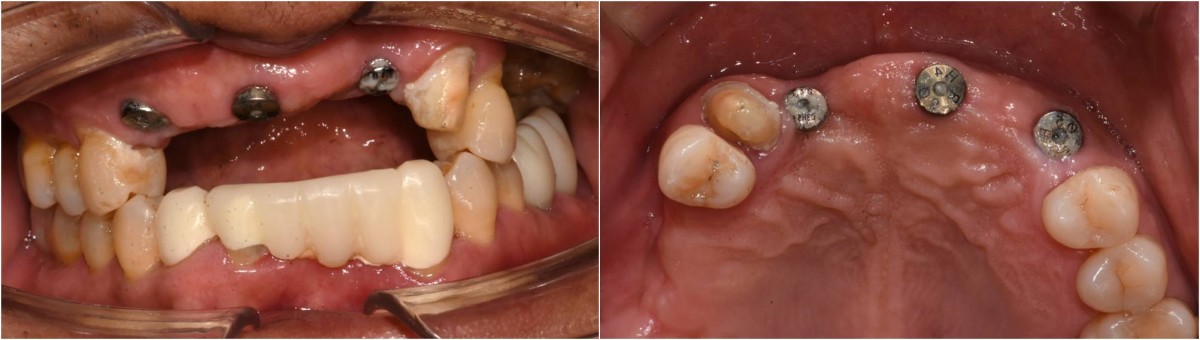

In the anterior maxilla, implant-supported fixed partial denture.

<GCpbc> A 58-year-old male is a patient undergoing implant installation in various parts. The old Br of the anterior maxilla has fallen

off and it is no longer possible to maintain it even temporarily, so a

treatment plan for the anterior teeth was made.